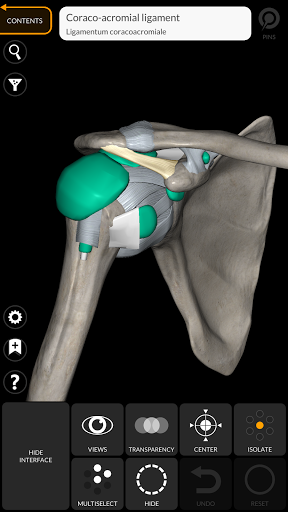

يتيح لك "Anatomy 3D Atlas" دراسة التشريح البشري بطريقة سهلة وتفاعلية.

من خلال واجهة بسيطة وبديهية، من الممكن ملاحظة كل بنية تشريحية من أي زاوية.

تتميز النماذج التشريحية ثلاثية الأبعاد بتفاصيل خاصة ودقة تصل إلى 4K.

• خيار إخفاء أو عزل نموذج واحد أو نماذج متعددة مختارة

• من خلال تحديد نموذج أو دبوس، يظهر المصطلح التشريحي ذي الصلة

وأضاف الأربطة